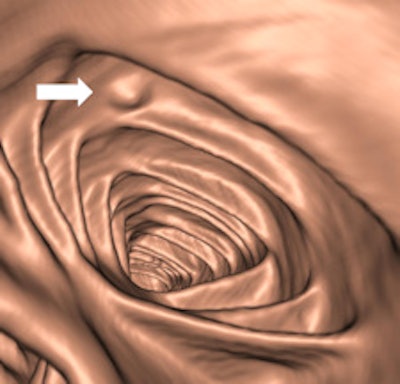

Left: Coronal reformatted view showing a pedunculated polyp of the sigmoid colon. Right: Volume-rendered endoluminal view of the same pedunculated polyp. In both images, the curved arrow indicates the stalk, and the straight arrow indicates the head of the polyp. Images courtesy of Andrea Laghi, MD.As an examination designed for polyp and tumor detection in the colon, CTC has now reached a sufficient level of competency, making the double-contrast barium enema an obsolete examination in 2011, according to fellow ECR presenter Dr. Philippe Lefere, a radiologist at Stedelijk Ziekenhuis in Roeselare, Belgium. As the implementation of CTC moves ahead, general radiologists must become aware this technique can play a significant role by scrutinizing both symptomatic and asymptomatic patients for polypoid and tumoral lesions in the colon.